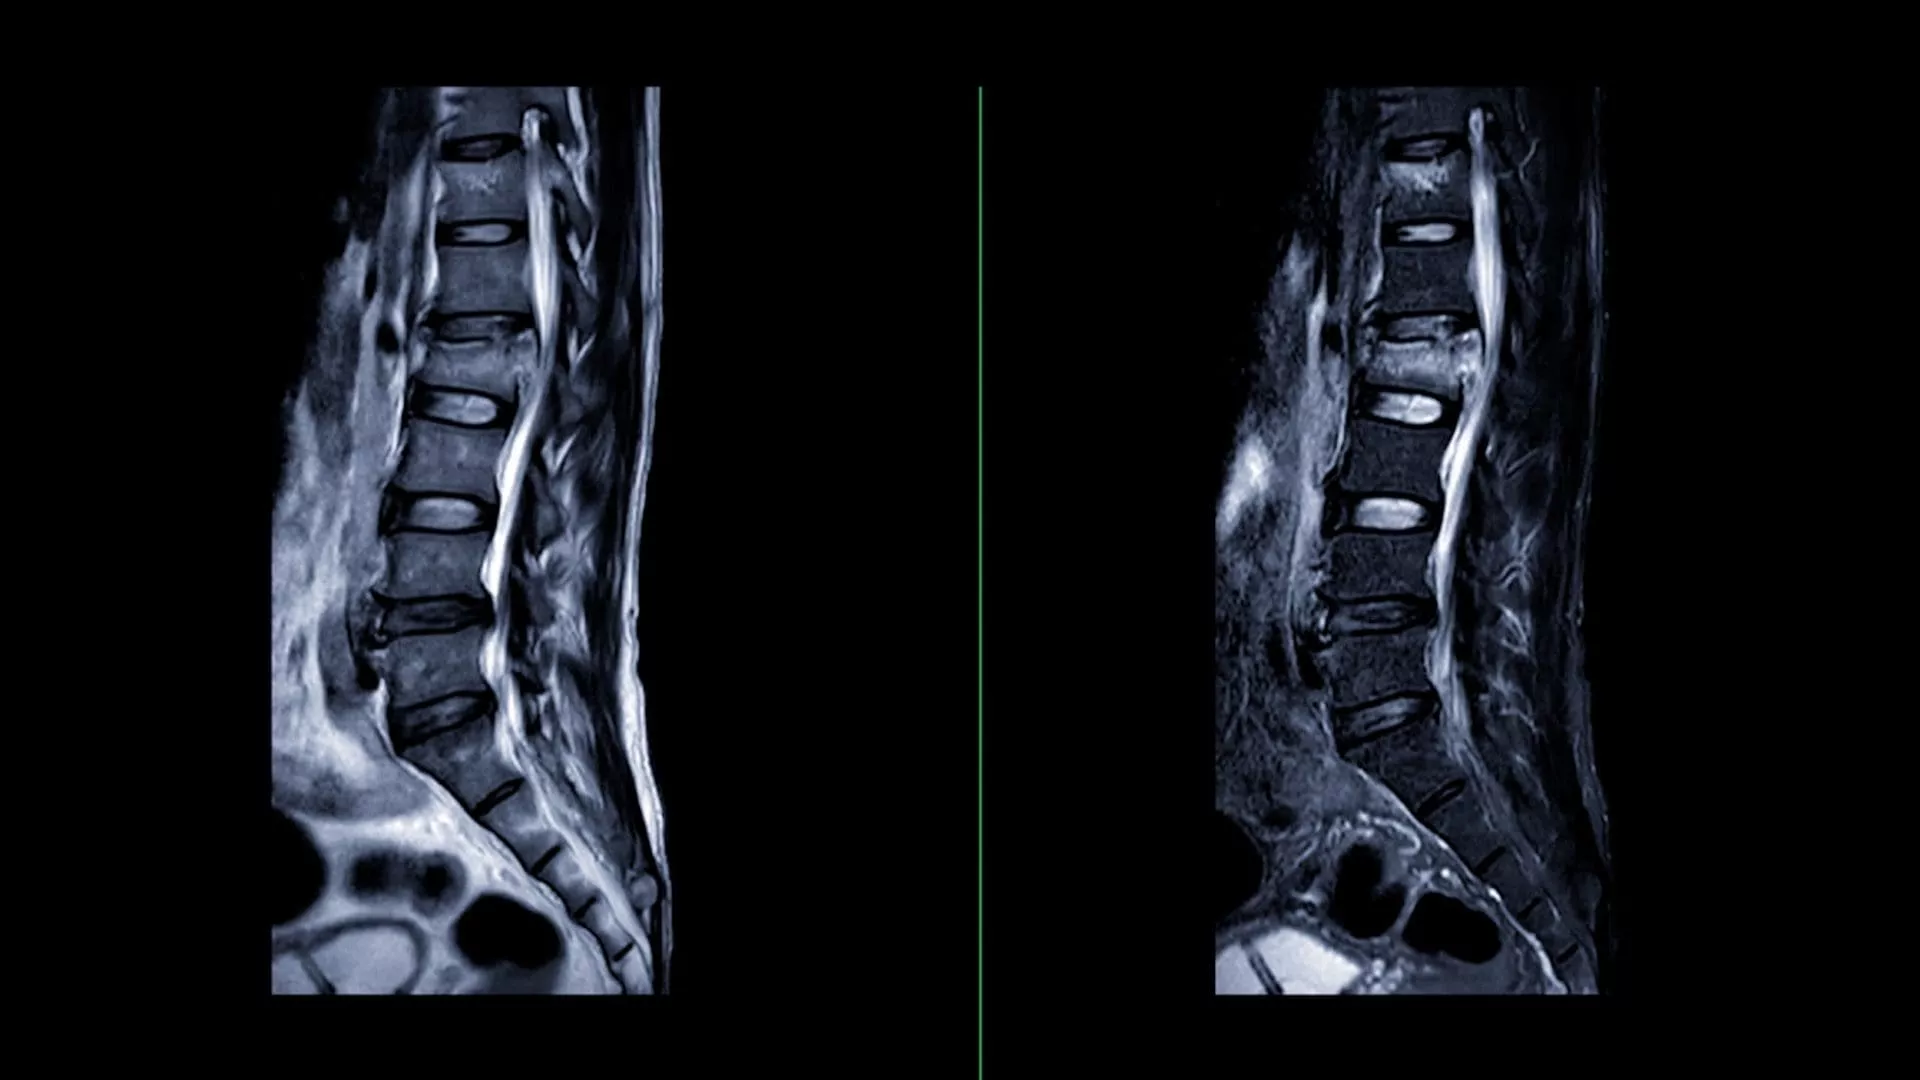

MR Lumbar Spine+ is an optional enhancement to your standard lumbar spine MRI. It uses advanced AI-enhanced technology to organize existing MRI images into clear, level-by-level measurements and annotated visuals—making spine findings easier to review and discuss with your provider.

A lumbar spine MRI is commonly used to help providers better understand the cause of back pain and related symptoms when other imaging or exams do not provide enough detail. MR Lumbar Spine+ builds on your standard MRI using AI-enhanced analysis to organize results into clearer, level-by-level spine insights that can make findings easier to understand and discuss.

No. MR Lumbar Spine+ does not change your lumbar spine MRI exam. It uses the same MRI images captured during your scheduled scan and applies advanced AI-enhanced analysis to organize them into clear, level-by-level measurements and annotated visuals that enhance how the results are presented.